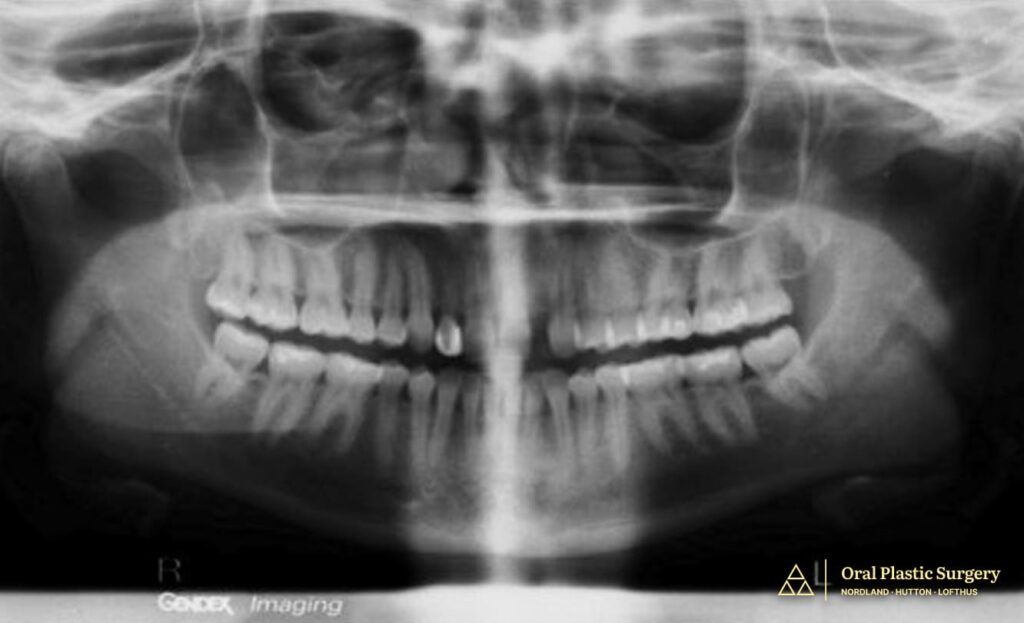

Dr. Lofthus performed a CBCT scan (3D imaging) to evaluate the ridge anatomy and determine whether implant placement was possible.

The scan revealed a common challenge in congenitally missing-tooth cases. Because the tooth never developed, the jawbone in that area never fully formed to normal thickness. Because the baby tooth had been missing for many years, the ridge had become too narrow and deficient for predictable implant placement.

In other words, the space was ready, but the bone was not.

Cone-beam computed tomography (CBCT) is essential in these cases because it reveals bone width, height, and density in three dimensions, information that cannot be accurately assessed from traditional 2D radiographs.

This allows the surgeon to measure the exact ridge dimensions and plan the appropriate volume and positioning of bone augmentation needed to support an implant long-term.